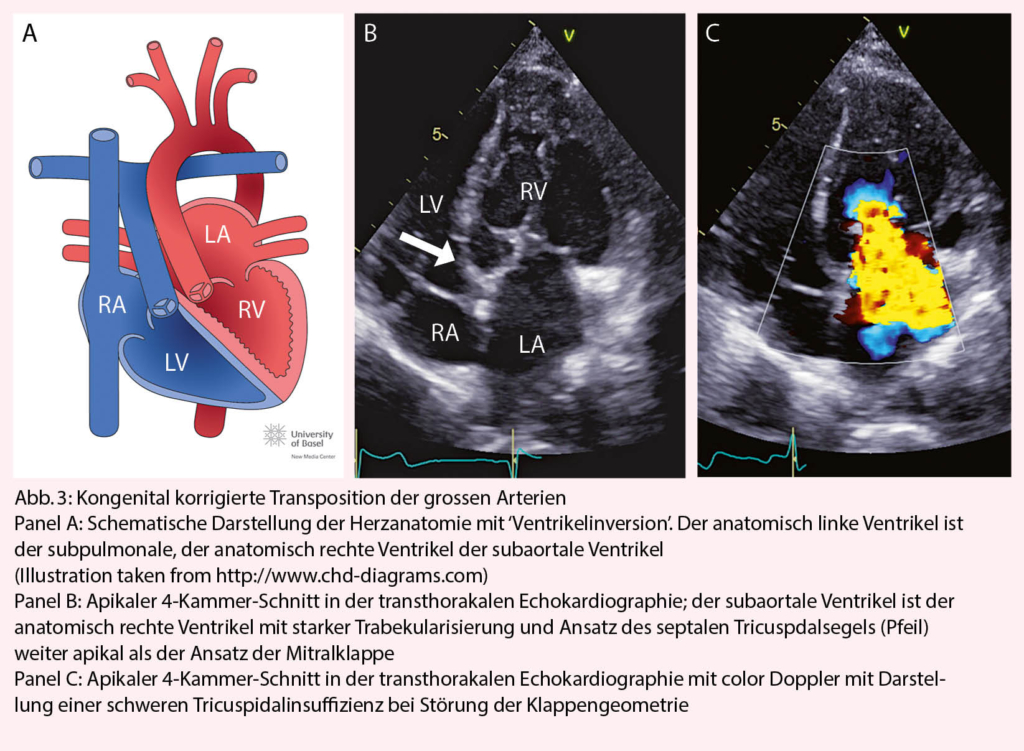

Die Ursache der kongenital korrigierten Transposition der grossen Arterien ist eine fehlerhafte ‘Faltung’ des Herzschlauches während der Embryonalentwicklung. Durch den L-loop kommt es physiologisch zur ‘Ventrikelinversion’. Das heisst, der rechte Vorhof konnektiert zum morphologisch linken Ventrikel, der linke Vorhof zum morphologisch rechten Ventrikel. Die Pulmonalarterie entspringt dem subpulmonalen linken, die Aorta dem subaortalen rechten Ventrikel (Abb. 3). Wenn zusätzliche Defekte vorliegen (am häufigsten sind Ventrikelseptumdefekte und die Pulmonalstenose) erfolgt die Diagnose meist im Kindesalter. Bei Fehlen zusätzlicher Defekte wird die Diagnose gelegentlich erst im Erwachsenenalter gestellt. Dann meist bei Auftreten von Komplikationen (progrediente Tricuspidalinsuffizienz, Herzinsuffizienz oder atrioventrikulärer Block). Die Betreuung solcher Patienten sollte in Zusammenarbeit mit einem spezialisierten Zentrum erfolgen.